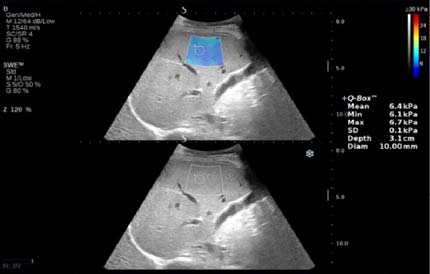

Представляем ряд клинических примеров, демонстрирующих определение степени фиброза печени с помощью SWE у беременных с HBV- и HCV-инфекциями (рис. 1–5).

Рис. 1. Беременная М.Н., G1P1A0, позитивна по вирусу гепатита В, результат сдвигововолновой эластографии печени: METAVIRSTAGE — F0

Обследование проводили в положении пациентки на спине с уклоном влево. Датчик располагали в восьмом-девятом межрёберном промежутке по правой передней и задней подмышечной линии. Плотность ткани определяли в правой доле на бессосудистом участке на глубине 2 см от капсулы, результаты выражали в килопаскалях. Полученные показатели плотности тканей оценивали по шкале METAVIR: <7,1 кПa — F0–F1; 7,1–7,9 кПa — F2; 8,0–10,4 кПa — F3; >10,4 кПa — F4), где F0 — отсутствие фиброза; F1 — расширение портального тракта без септ; F2 — портальный фиброз с небольшим количеством сформированных септ; F3 — портальный фиброз с формированием множественных септ; F4 — цирроз печени.